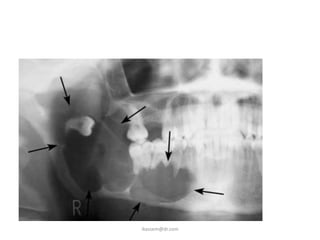

F. Odontogenic cyst and Tumors

• The dental follicle may

undergo cystic

degeneration and

become a dentigerios

cyst or keratocyst.

• A meloblastoma may

developed from

epithelium within the

dental follicle

ikassem@dr.com

G. Fracture of the jaw

• impacted third molar

occupies space that is

usually filled with bone,

this weaken the

mandible and render

the mandible to

fracture.